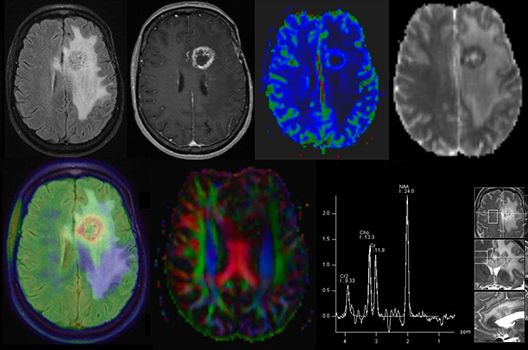

Die Schwerpunkte in der MR-Forschung liegen in der multiparametrischen und funktionellen Bildgebung bei onkologischen und anderen, neuroradiologischen Fragestellungen und umfassen die Anwendung modernster MR-Verfahren sowie die Untersuchung an Hochfeld-Geräten.

Die Magnetresonanztomographie (MRT) ist ein Verfahren, bei dem durch magnetische Kräfte Bilder des Körperinneren angefertigt werden. In der Neuroradiologie können manchmal kleinste Veränderungen schwere Folgen haben; daher forschen wir an der Entwicklung hochauflösender MRT-Sequenzen, mit denen diese Prozesse und auch einzelne Nervenfaserbahnen sichtbar gemacht werden können. Darüber hinaus sind bei vielen Erkrankungen des Gehirns die Blutgefäße betroffen. Daher arbeiten wir an der Neu- und Weiterentwicklung von MRT-Sequenzen zur Darstellung der Blutgefäße und zur Blutflussanalyse (sog. „Angio-MRT“). Einen besonderen Forschungsschwerpunkt unserer Klinik stellen die MR-Protonenspektroskopie und die funktionelle MRT dar, mit denen die Analyse einzelner chemischer Substanzen im Hirngewebe oder die Darstellung ausgewählter Hirnfunktionen möglich ist.

- PET/MRT in der Neuroonkologie

Die Hybridbildgebung mittels PET/MRT spielt insbesondere in der onkologischen Bildgebung eine wichtige Rolle. Eine mögliche Fragestellung ist die Unterscheidung zwischen einem Tumorrezidiv oder therapeutisch assoziierten Veränderungen insbesondere dann, wenn diese Frage mittels MRT alleine nicht beantwortet werden kann.

Die bildgebende Diagnostik und Verlaufsbeurteilung von Tumoren des Nervensystems ist einer der klinischen und Forschungsschwerpunkte unserer Abteilung. Eine besondere Bedeutung kommt der Hybrid-Bildgebung zu. Das Universitätsklinikum verfügt über einen integrierten Ganzkörper-PET/MRT-Scanner, der die Vorteile der MRT-Bildgebung und der Positronenemissionstherapie (PET) vereinigt. Aufgrund der langjährigen klinischen Arbeit und Forschungstätigkeit mit diesem Gerät hat die Neuroradiologie Tübingen maßgeblich zur Etablierung dieses Verfahrens beigetragen. Auch weiterhin forschen wir intensiv an neuen Methoden zur frühen Einordnung von Tumoren und insbesondere Tumorrezidiven, die mit anderen Methoden häufig nicht erfasst werden können.